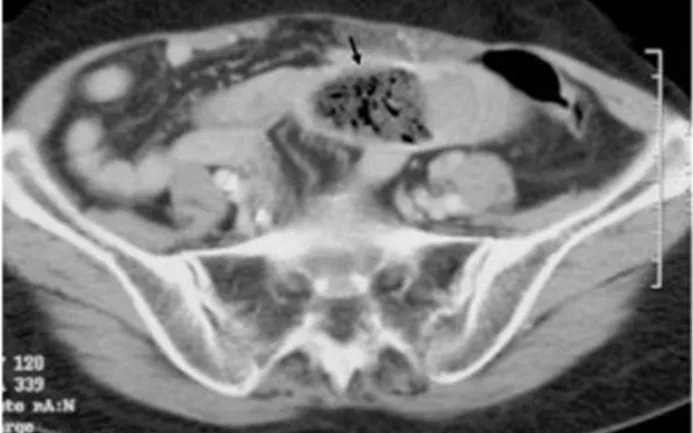

Qua thăm khám lâm sàng và các phương tiện chẩn đoán hình ảnh, bác sĩ phát hiện trong dạ dày bệnh nhân có một khối bã thức ăn lớn, đồng thời một khối khác gây tắc ruột non. Tổn thương xuất hiện ở hai vị trí khiến ca bệnh trở nên phức tạp, buộc các chuyên khoa phải phối hợp để lựa chọn phương án điều trị hiệu quả nhưng vẫn bảo đảm an toàn và hạn chế xâm lấn.

Sau đó, ê-kíp Ngoại khoa tiếp tục phẫu thuật nội soi ổ bụng để xử lý khối bã gây tắc ruột non. Các bác sĩ xác định chính xác vị trí tắc, mở một đường nhỏ khoảng 3cm, đưa quai ruột chứa bã ra ngoài để lấy dị vật, đồng thời bảo tồn tối đa cấu trúc và chức năng của ruột. Nhờ áp dụng phẫu thuật nội soi, bệnh nhân ít đau sau mổ, sớm vận động và nhanh chóng ăn uống trở lại.